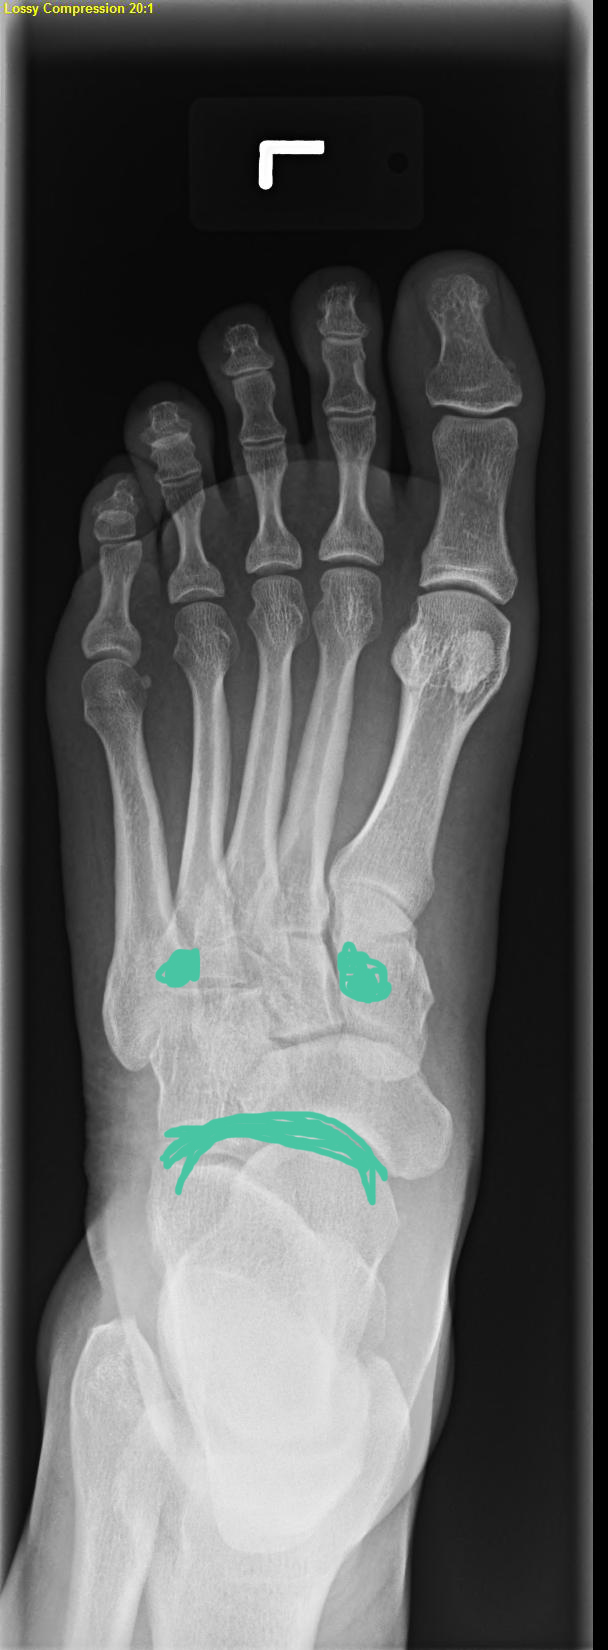

The gist of it comes down to a couple of things. 1) The tendonitis in my foot may not be tendonitis but a possible stress fracture. 2) I had an emergency kidney stone procedure last Friday.

Now on to the foot. My regular followers know that my foot issues have been ongoing for sometime. After the pain became so severe during the Bronx 10 miler I finally decided I had enough and made an appointment with a sports doctor.

It could be a possible stress fracture, or maybe not, but we will know for sure after we get the results back from my upcoming MRI. We need proof!